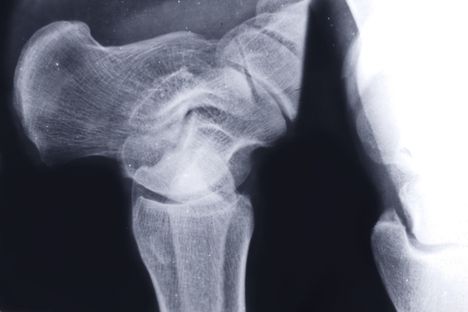

D-vitamiinin puutteen on havaittu olevan yhteydessä esimerkiksi lonkkamurtumiin. D-vitamiini kannattaisi mitata verestä kesäkauden ulkopuolella. Kuva: Colourbox

D-vitamiinin puutteen on havaittu olevan yhteydessä luun pieneen mineraalitiheyteen, suurentuneeseen kaatumisriskiin ja lonkkamurtumiin.